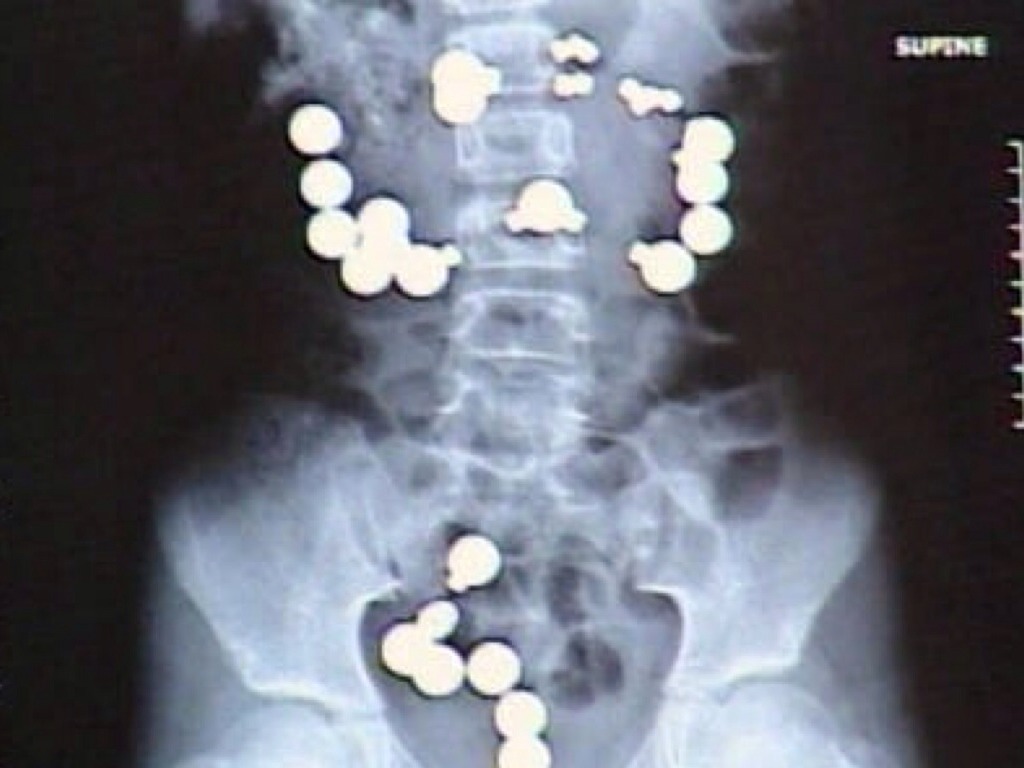

Man steals ring!

WHAT DID I SWALLOW?